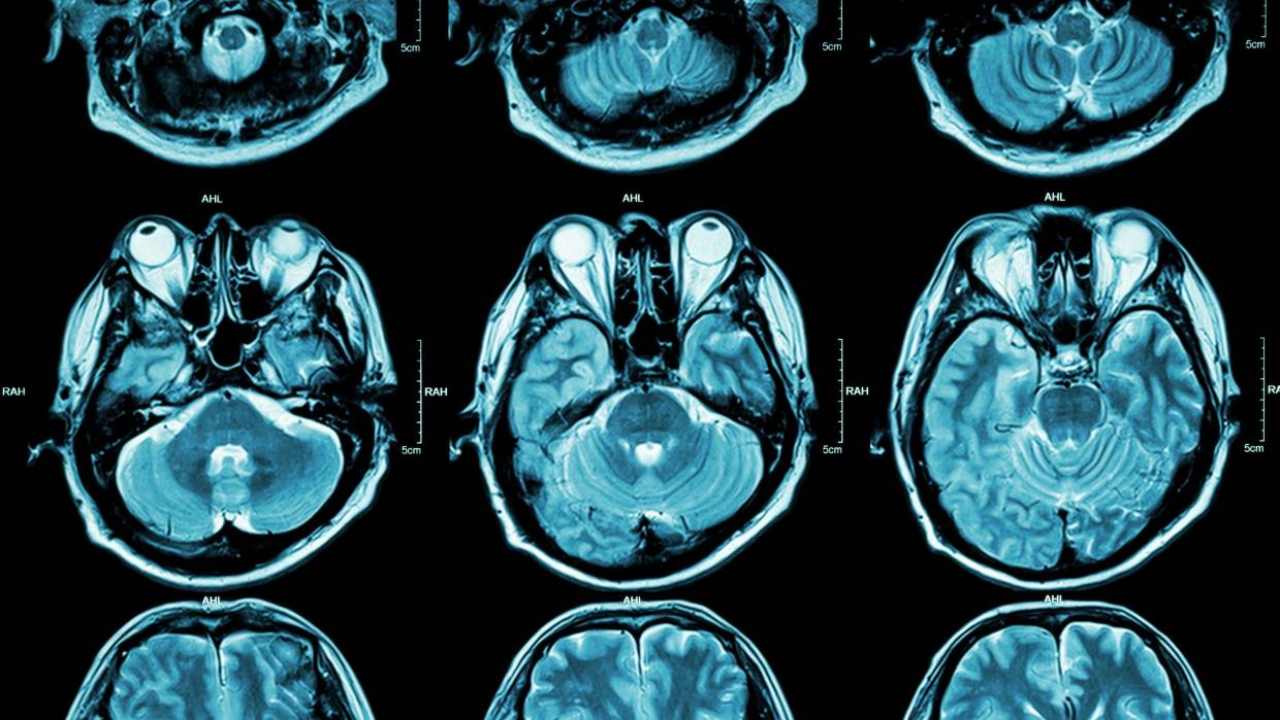

by researchers from Yale and to her institutions’ colleagues suggests, specific genes influence depression to an extent of posttraumatic stress disorder, bipolar disorder and even schizophrenia. Though explaining anxiety, depression and other mental health issues might not be possible yet, traces of certain genes’ risk factors have been confirmed. Joel Gelernter, co-lead author and professor of Psychiatry believes that this is the most useful outcome till date from a study around anxiety. [caption id=“attachment_6942731” align=“alignnone” width=“1280”]